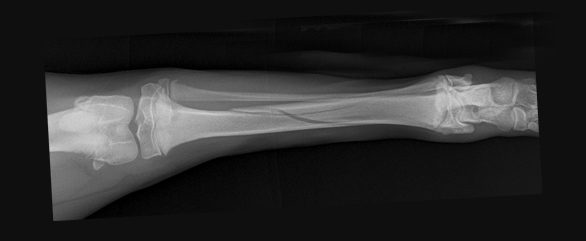

Surgery aims to realign and stabilise the fractured bones to allow uneventful healing. There are numerous methods used to stabilise the fractured bone including the use of plates, screws, pins, and wire. These are hidden from view and placed under the skin (internal fixation).

Drag the circle to view before and after surgery images.